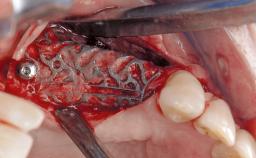

Late Presentation of Peri-Implant Mucositis Requiring Soft-Tissue Augmentation and Esthetic Crown Lengthening at Implant Site 11

Biological or technical complications around implant-supported prostheses place a significant burden on patients as well as the surgical and restorative team. Inflammation of the peri-implant soft tissues is often the first sign that something has gone awry. While there is never a good time for a complication, late presentation of inflammation in the soft tissues around a long-standing prosthesis triggers a period of research and review of the case in order to ascertain the treatment history and its possible contribution to the etiology of the situation. This becomes more complicated in situations where a patient has not received regular maintenance and clinical/radiographical examinations due to personal, financial, or professional reasons. When the complication occurs in the esthetic zone, the complexity of the situation expands exponentially, as the only acceptable outcome in the patient’s eyes will be the maintenance of the esthetics of the prosthesis.

Soft Tissue Grafting -